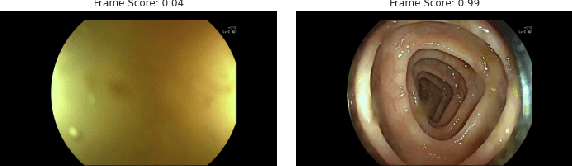

We propose a two-stage unsupervised approach for parsing videos into phases. We use motion cues to divide the video into coarse segments. Noisy segment labels are then used to weakly supervise an appearance-based classifier. We show the effectiveness of the method for phase detection in colonoscopy videos.